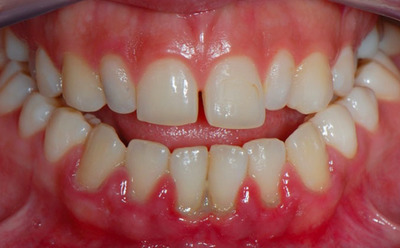

Локальный острый

Острый пародонтит встречается достаточно редко. Начинается заболевание резко, практически без начальных симптомов. Характеризуется острой болью при чистке зубов и жевании. Дёсны воспаляются, появляется кровоточивость. Чаще всего пародонтит этой стадии локализован, то есть распространяется на несколько зубов, а не на весь ряд.

К возникновению заболевания приводят патогенные микробы, механические и химические воздействия, а также неправильная установка пломбы или травма десны.

Фото 1. Острый локальный пародонтит. Воспалены десны в области двух зубов, наблюдается покраснение и кровотечение.

Диагностика острого пародонтита происходит быстро. Выявить заболевание можно уже на этапе простого осмотра специалистом. Чаще всего, острый пародонтит успешно вылечивается. Риск рецидива практически равен нулю.